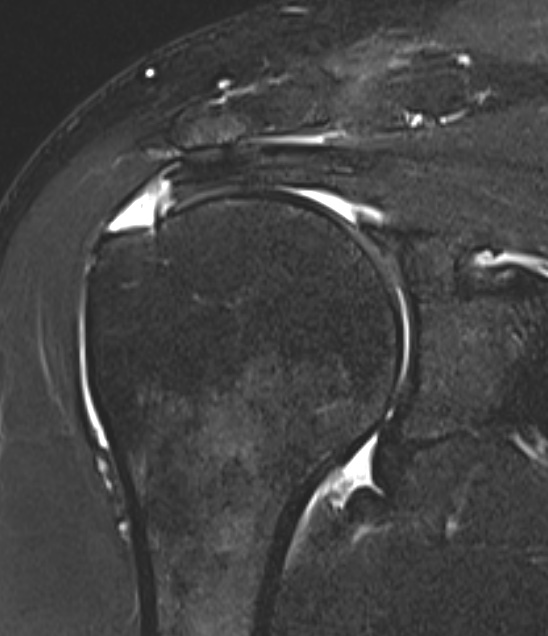

MRI

Look for

- supraspinatus / infraspinatus / subscapularis / long head of biceps pathology

- partial verus full thickness

- size of tear in coronal and sagittal planes

- retraction

- atrophy / fatty infiltration

Full thickness rotator cuff tears